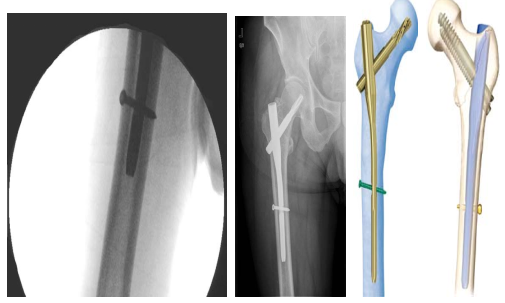

二 股骨粗隆间骨折的治疗首选股骨近端髓内钉固定(PFNA/Intertan)

髓内固定属于中心性固定不需要对内侧骨块解剖复位固定,不干预内侧的生物学环境,自然增加了骨折的愈合率。因此,髓内固定适于任何类型的骨折固定,特别是在不稳定型骨

折固定中表现优异。

◆ 疼痛减轻后开始下地,从不负重锻炼,到助行器辅助下部分负重锻炼,直至完全负重,对于骨水泥型假体,根据骨质疏松情况,4 ~ 6 周可过渡至完全负重,生物型假体在

8 ~ 12 周过渡至完全负重。